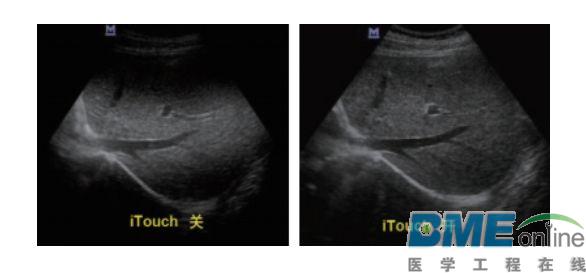

设备型号DP-50 全自动便携式超声诊断系统(迈瑞),该设备为DP 系列超声的较高级版本,具有iTouch 图像一键优化、 iBeam 复合成像、iClear 斑点噪声抑制、宽带频移谐波等技术。

iTouch图像一键优化: